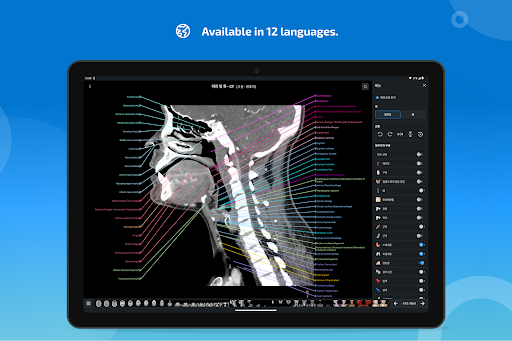

-The Korean language is now available for the app and the anatomical structures.